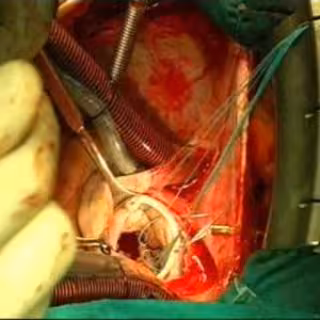

Durante la exposición del caso, Infante explicó que dicha técnica diagnóstica, que se viene empleando para otros tejidos y órganos desde 1992, "aunque nunca para biopsiar un tumor cardíaco", permitió detectar en una fase primaria --temprana-- una masa tumoral originada en el pericardio "con una longitud de 17 centímetros, una anchura de ocho centímetros y un espesor máximo de cinco centímetros".

Por su parte, el doctor Rafael Romero, miembro de la Unidad de Endoscopia y encargado de dirigir la punción para la toma de la biopsia, explicó que tras una valoración inicial se decidió realizar la ecoendoscopia a la paciente, "la cual se introdujo por la boca y ya desde el esófago se hizo la biopsia con una aguja fina y con control de anestesista", explicó a Europa Press.

Añadió que tras la prueba endoscópica, que se realizó el pasado 30 de agosto y que duró apenas 10 minutos, la paciente permaneció 24 horas en Observación y monitorizada en la Unidad Coronaria, al objeto de controlar el comportamiento del corazón. Posteriormente, en concreto el 28 de septiembre, la paciente fue operada "mediante una cirugía rutinaria que no duró más de 45 minutos", prosiguió Infante.